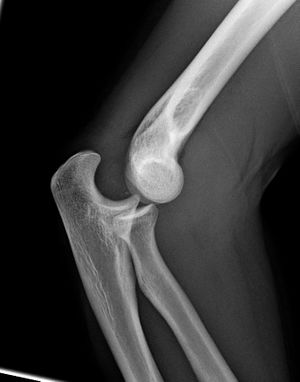

المرفق إنگليزية: Elbow هي عظمة مفصلية تربط عظمة العضد مع عظمتي الزند و الكعبرة. وتكون أماكن الالتقاء الثلاثة، ثلاثة مفاصل أصغر وتسمح هذه المفاصل الصغيرة بحركات معينة، حيث يسمح مفصلا العضد ـ الزند والعضد ـ الكعبرة للشخص بثني الساعد إلى أعلى وأسفل، بينما يسمح مفصلا الكعبرة ـ الزند والعضد ـ الكعبرة بدوران الساعد وكذلك راحة اليد أعلى وأسفل.

يحيط بمفصل الكوع كبسولة من نسيج متين. وتقوم هذه الكبسولة مع عدد من الأنسجة القوية الحبلية الشكل التي تُعرف بالأربطة بالمحافظة على العظام في أماكنها. ويعمل السائل الزيلي بمثابة مزلق لتقليل الاحتكاك عند الكوع.

يتسبب الالتواء الزائد أو العنيف للساعد في إصابة أربطة الكوع، أو السائل الزليلي. تسمى هذه الإصابة كوع التنس لأنها كثيرًا ما تحدث في لعبة التنس. وقد تحدث زحزحة للكوع إذا ما سقط شخص ما على ذراعه الممتدة.